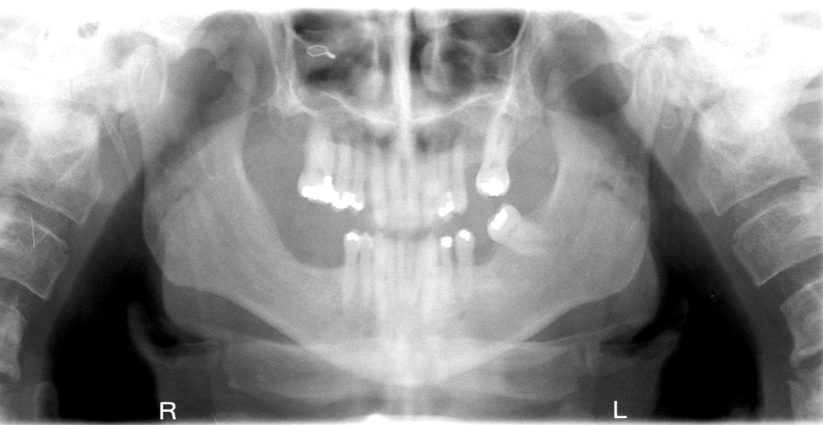

What is wrong with this image?

A

glasses